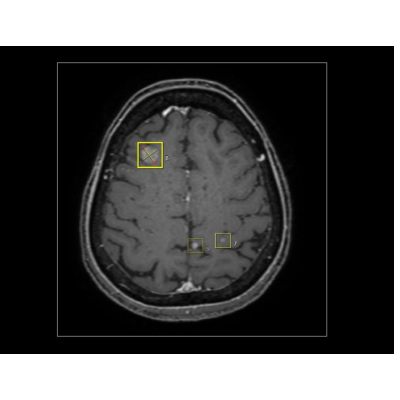

联影智能MR脑转移瘤智能分析系统可辅助检出颅内转移瘤病灶,提供病灶长短径和位置分析结果,自动生成影像所见,辅助医生筛查诊断,提高整体阅片效率,减少漏诊情况,有效辅助癌症疾病进程评估以及治疗方案选择。

联影智能MR脑转移瘤智能分析系统可辅助检出颅内转移瘤病灶,自动显示病灶所在层面、大小及位置等多维信息,帮助影像科医生提高检测敏感性、避免漏诊。经过多中心验证及多医生读片对比实验结果显示:联影智能MR脑转移瘤智能分析系统病灶检出敏感度超93%,同时完美平衡假阳性,在AI辅助下医生阅片脑转移灶检出敏感度平均提升20%以上,每例平均节省40%阅片时间。